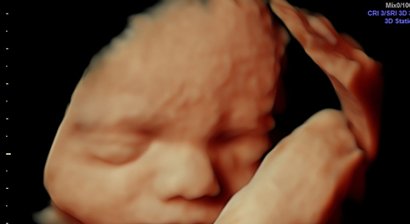

3D/4D Ultraschall

Bei meinen Patientinnen wird bei guter Kindslage auf Wunsch auch ein 3D Bild angefertigt. Aus Termingründen ist es mir NICHT möglich für "ordinationsfremde" Patientinnen diese Untersuchung anzubieten! Ich bitte hierfür für Verständnis!